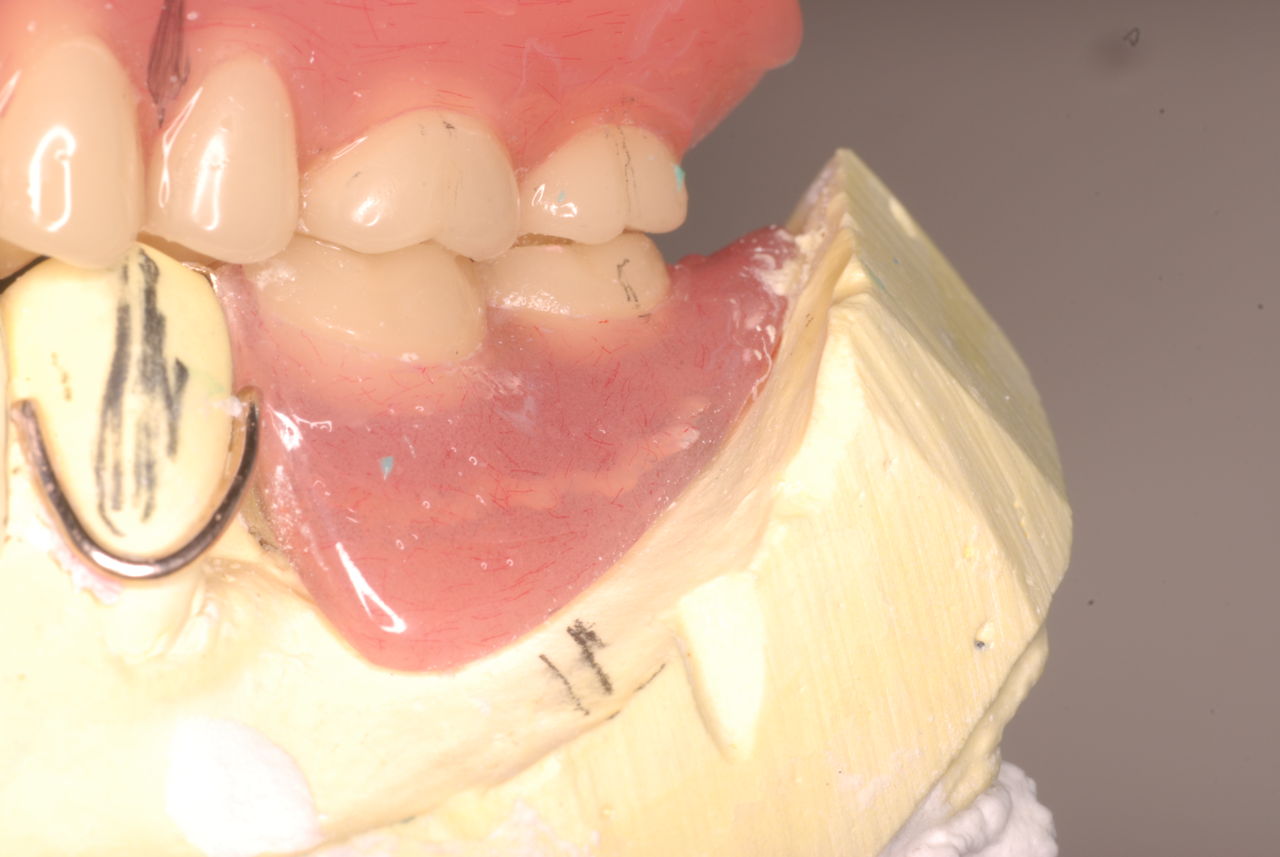

下顎です。

上の総義歯はまっったくはずれませんでした。下顎の入れ歯では若干痛みが出そうなので噛み合わせの調整をしています。口腔内では時間がかかりすぎるので器械に付けて調整しています。

下顎が右にシフトしているので噛み合わせはとても慎重にしました。下の方が頬側にないと安定せず噛めないのです。

左側の噛み合わせはまともにできます。